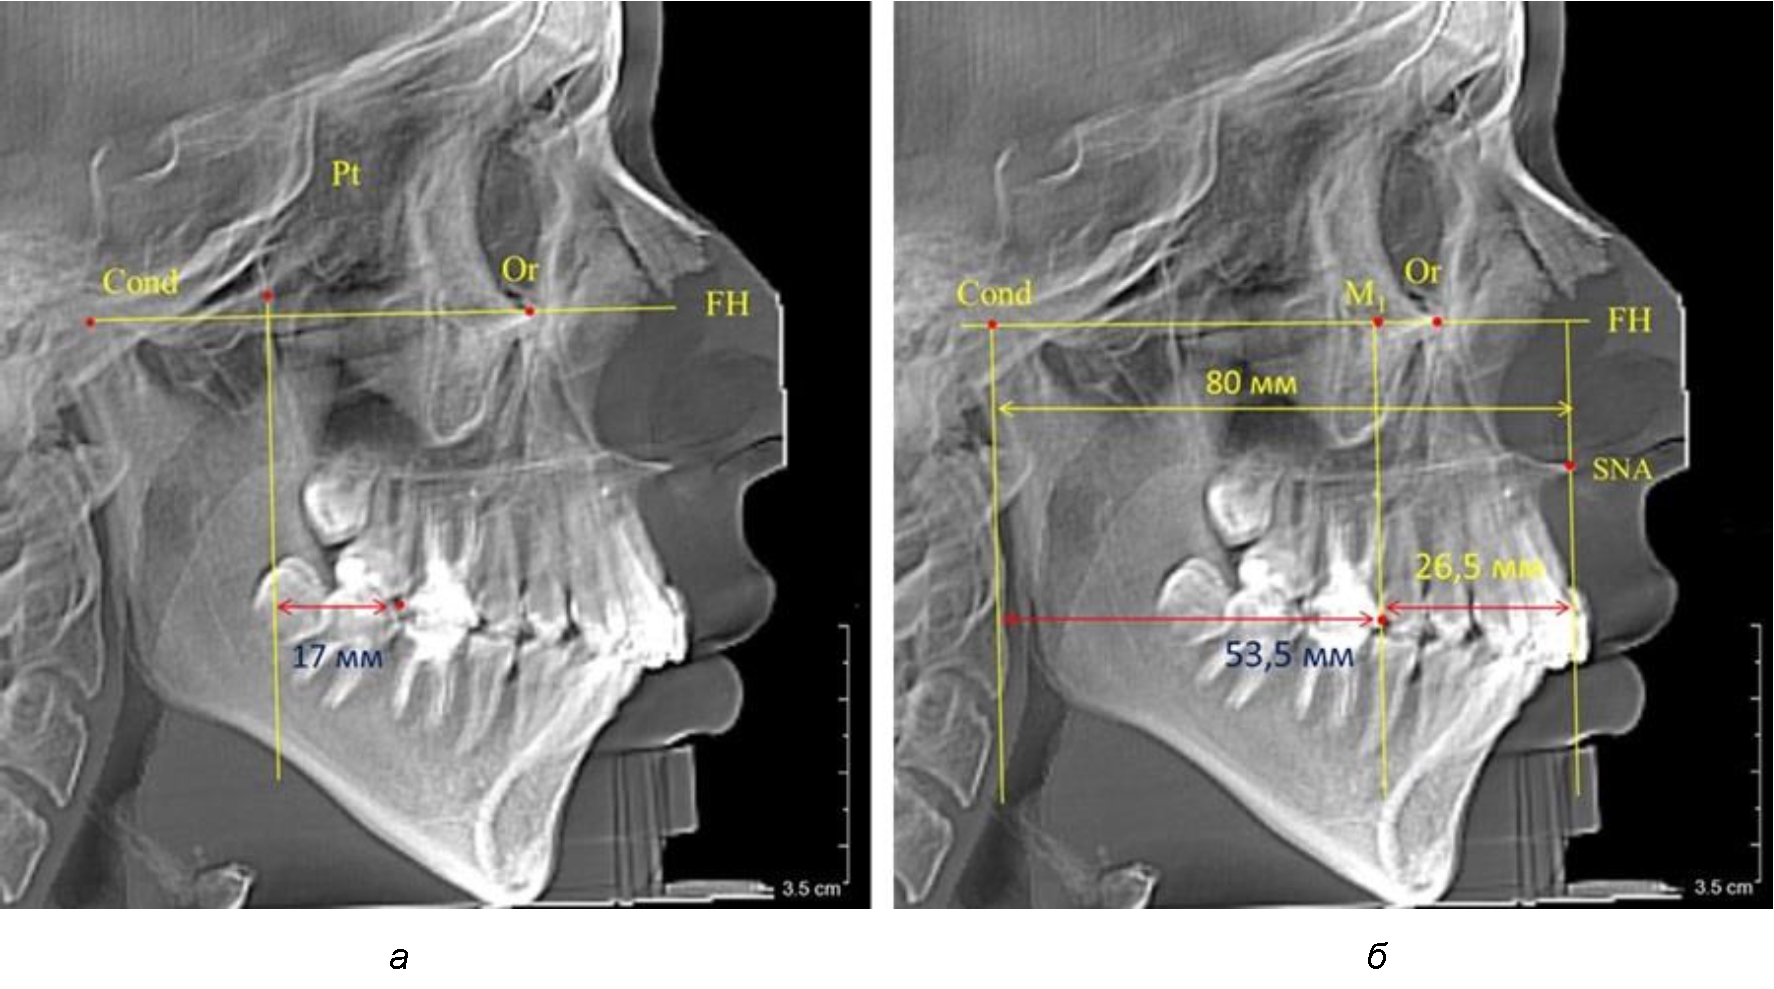

Так, при расстоянии от крыловидной вертикальной плоскости PTV до дистальной поверхности верхнего первого постоянного моляра в 13 мм сагиттальный размер гнатического отдела был 82 мм. При этом отношение кондилярно-спинального расстояния к кондилярно-молярному размеру (54,5) было близким к коэффициенту 1,5, что представлено на рис. 2.

В то же время при увеличенном расстоянии от крыловидной вертикальной плоскости PTV до дистальной поверхности верхнего первого постоянного моляра, равное 23 мм, сагиттальный размер гнатического отдела составил 92 мм. При этом отношение кондилярно-спинального расстояния к кондилярно-молярному размеру (30,5), так же, как и при малых размерах, было близким к коэффициенту 1,5, что представлено на рис. 3.

Рис. 2. Особенности положения первых моляров по R. E. McDonald (а) и по предложенному методу (б) при уменьшенном молярно-крыловидном расстоянии

Рис. 3. Особенности положения первых моляров по R. E. McDonald (а) и по предложенному методу (б) при увеличенном молярно-крыловидном расстоянии